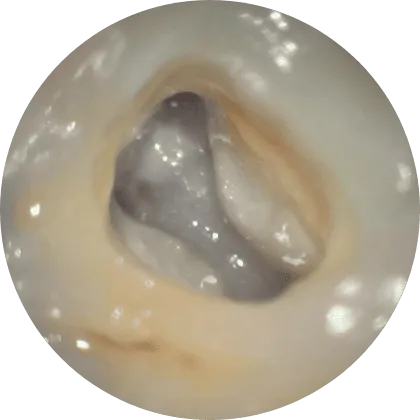

マイクロスコープと

肉眼での見え方の違い

肉眼では暗く細い根管内部は、手指の感覚や経験に頼らざるを得ない部分もあります。

一方、マイクロスコープを使用すると、根管の入り口や細かく枝分かれした部分、微細な亀裂、残った感染物質まで鮮明に確認可能。視野が広がることで、必要な部分を正確に処置でき、不要な削合を抑えながら再発リスクを減らすことができます。

肉眼

肉眼で

根管内を見た場合

マイクロスコープ

マイクロスコープで